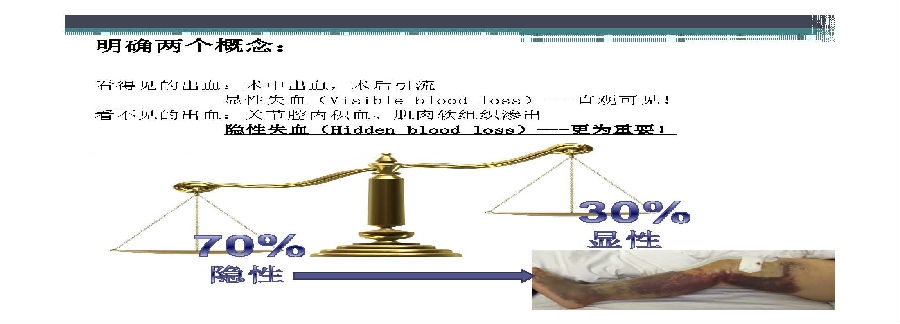

对于关节外科而言快速康复实际上是以病人加速舒适康复为目的,加强围术期的综合管理,包括疼痛和睡眠管理、血栓预防管理、感染预防管理、围术期血液管理,减少放置引流管、尿管、减少止血带应用,减少术后恶心呕吐,尽早进食,尽早康复等,逐步达到无血、无痛、无栓、无感、无肿、无管、无吐、无带等优良效果。为此,小编特邀王坤正教授等多位关节外科的专家参与撰写快速康复外科在关节外科的应用的主题文章,共话“人工关节置换快速康复”新理念,探讨建立符合我国特色的关节置换围手术期管理与快速康复体系,促进我国关节外科技术整体发展与提高。